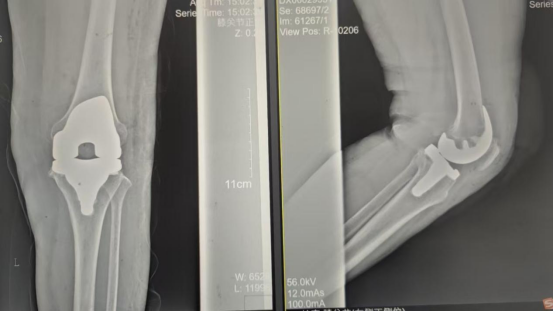

术后影像资料

因张女士患有高血压病2级(高危)、心律失常(窦缓)且伴有肺部感染等并发症。穆志亮主任和叶龙安主治医师根据张女士的病情制定详细手术方案,建议在全麻下行“左人工全膝关节置换术”。

手术当天张女士怀着忐忑的心情进入手术室,然而伴随着麻醉医师的和蔼交谈和手术护士的温馨叮咛,在不知不觉中慢慢睡着,手术非常顺利。术后经医护人员的精心治疗与护理,张女士康复出院,最终解决了10余年的病痛。